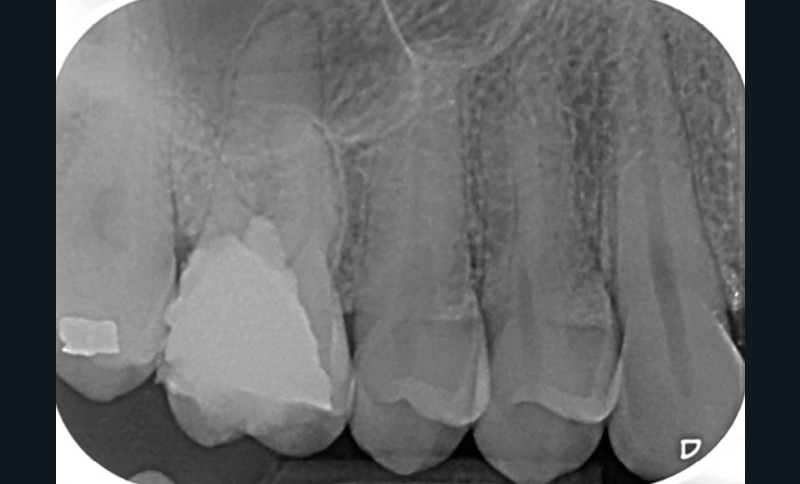

Perforation supra-osseuse (fig. 1)

Les perforations supra-crestales sont la plupart du temps iatrogéniques et surviennent lors de la réalisation de la cavité d’accès, ou de la recherche des entrées canalaires. Il s’agit généralement d’une communication avec un diamètre bien défini et aux contours nets. De ce fait, ce type de perforation est appelée « perforation à quatre parois ». Les perforations peuvent également être d’origine pathologique (résorption cervicale externe, carie active).